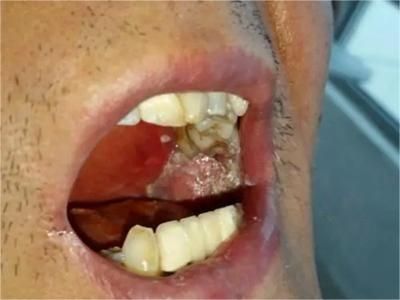

牙龈癌多源于牙间乳头及龈缘区,溃疡呈表浅、淡红,以后可出现增生。由于黏骨膜与牙槽突附着甚紧,较易早期侵犯牙槽突骨膜及骨质,进而出现牙松动,并可发生脱落。X线片可出现恶性肿瘤的破坏特征虫蚀状不规则吸收。

牙龈癌常发生继发感染,肿瘤伴以坏死组织,触之易出血。体积过大时可出现面部肿胀,浸润皮肤。